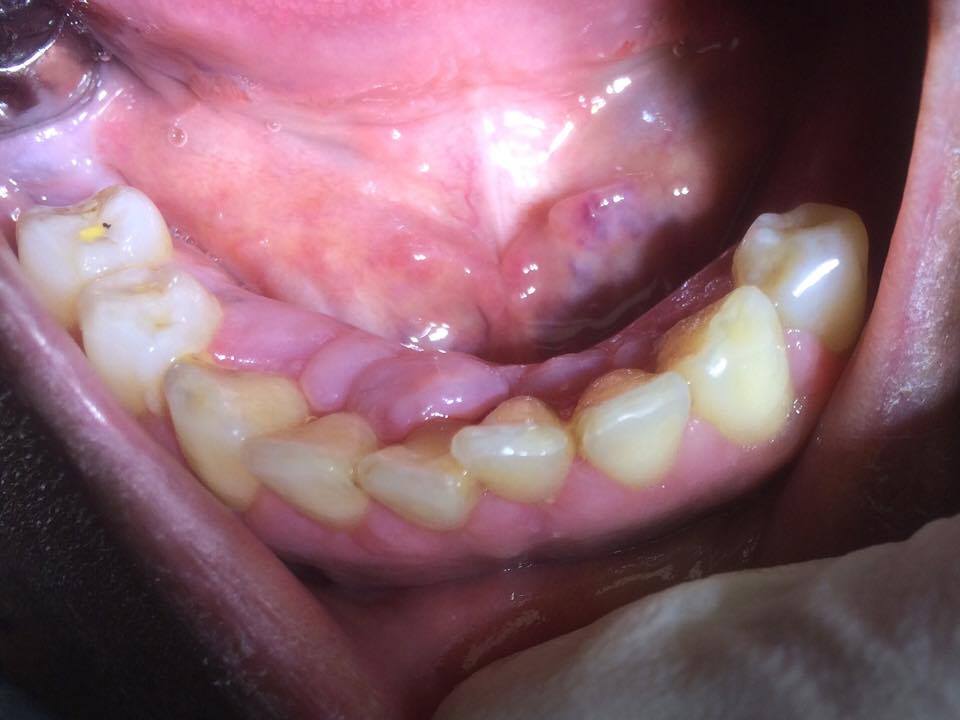

Patiente 47 ans d'origine africaine est adressé par son médecin traitant pour une hyperplasie gingivale en secteur antérieur mandibulaire.

Je pense à une hyperplasie gingivale d'origine médicamenteuse (inhibiteur calcique) sur facteurs locaux aggravants (mauvaise HBD, maladie parodontale chronique)

Au rdv de réévaluation, l'hypertrophie gingivale s'est nettement résorbée. La thérapeutique est favorable.